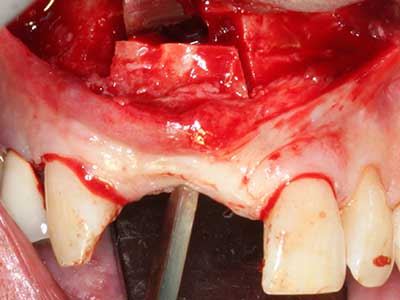

Fig. 17a: CT image of a growth-promoting osteotomy immediately adjacent to ...

Abb. 17b: the alveolar duct with nerve irritation (lateral and coronal view).

Fig. 18: Preparation of a cortical cover with the piezo bone saw (Piezomed, W&H).